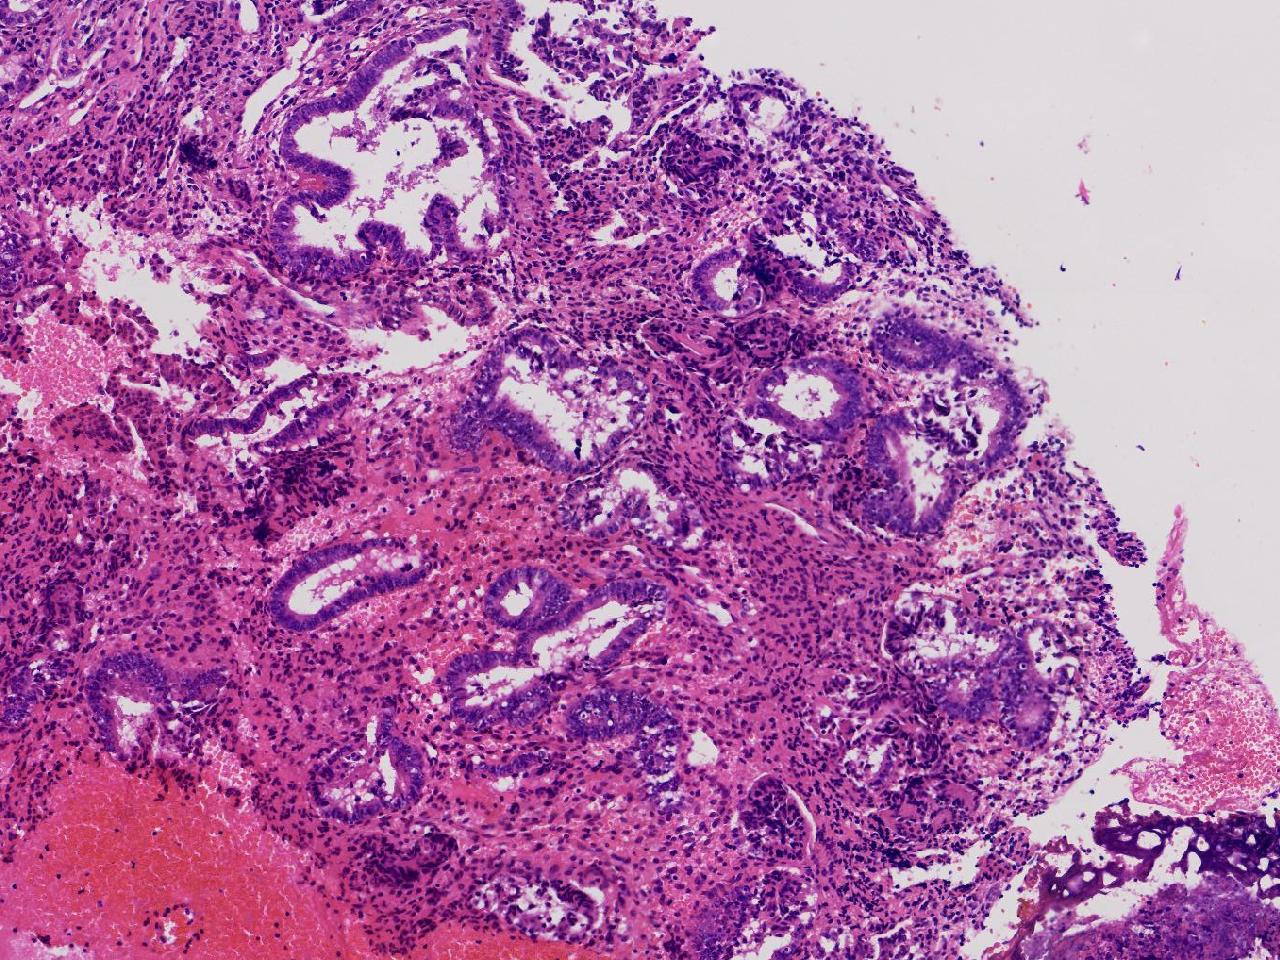

性别

女

年龄

55岁

女,55岁,月经紊乱4年,彩超示:子宫内膜增厚(内膜厚15.7mm),末次月经:2025年7月27日。

标本名称

宫腔镜下子宫内膜活检

大体所见

灰粉色不整形软组织多块,1.5X0.8X0.6厘米。

考虑:子宫内膜增生伴子宫内膜炎

子宫内膜增生紊乱,内膜息肉样结构